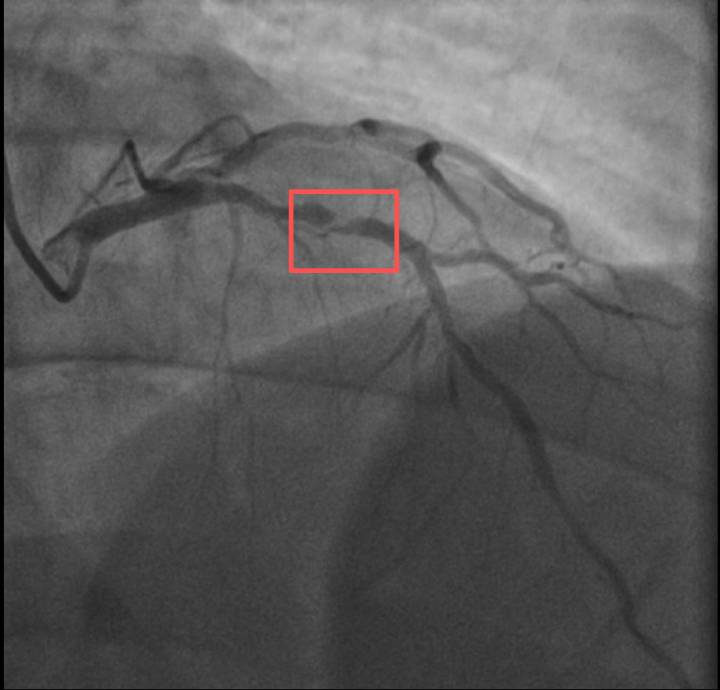

介入治疗后影像图

浙江医院心血管内科的医生分析,剧烈运动导致这位患者心脏的不稳定斑块破裂,进而造成前降支近段次全闭塞。所幸送医及时,孙先生的身体险情被化解。